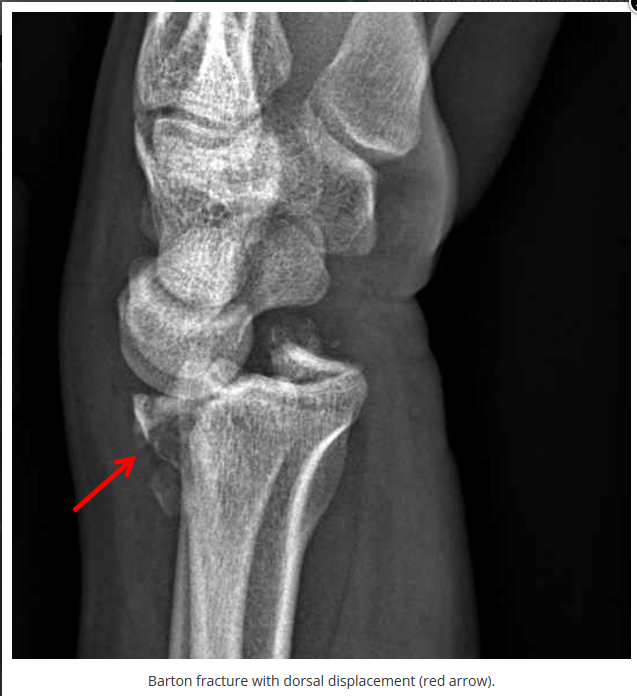

这些腕与手的骨折X线片如果没有标注箭头,你还能识别出来吗?

X线读片是骨科医生的基本功。

今天是腕部与手的X线片。所有X线片都

带有标注和说明

,可以选择长按图片,

自动翻译相关说明

。